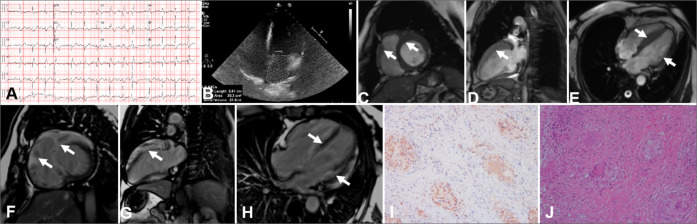

Cardiac sarcoidosis (CS) represents a rare yet potentially life-threatening condition characterized by non-specific clinical symptoms that maybe easily missed by clinicians. In this case series, the clinical presentations, various imaging modalities' characteristics, and the management of four patients, each with distinct phenotypes of CS confirmed through endomyocardial biopsy, are discussed. Advanced imaging techniques, including positron emission tomography, revealed the focal septal uptake of 18F fluorodeoxyglucose, which suggests an ongoing inflammation, whereas contrast-enhanced cardiac magnetic resonance demonstrates septal late gadolinium enhancement, which indicates replacement fibrosis. These features of multimodality imaging in CS can assist in patient diagnosis and treatment.